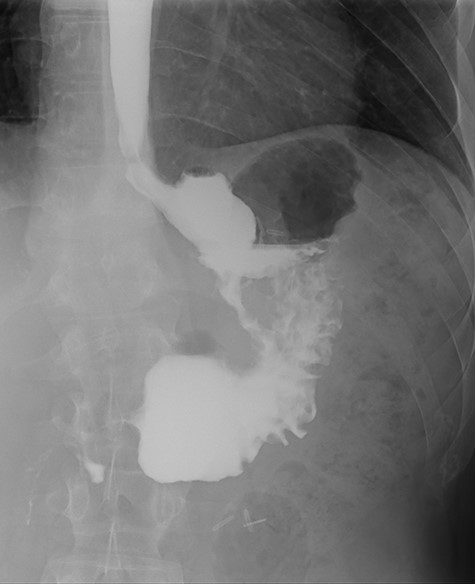

After treatment of the abdominal abscess with percutaneous drainage and antibiotics, an upper GI contrast swallow study confirmed persistency of the GGF without any spillage of contrast to the abdominal cavity (see Fig. 9). The patient was discharged, medicated with oral PPIs.

Upper gastrointestinal contrast swallow study image showing progression of contrast from the oesophagus to the gastric pouch and from the gastric pouch to the excluded stomach, confirming a gastro-gastric fistula.